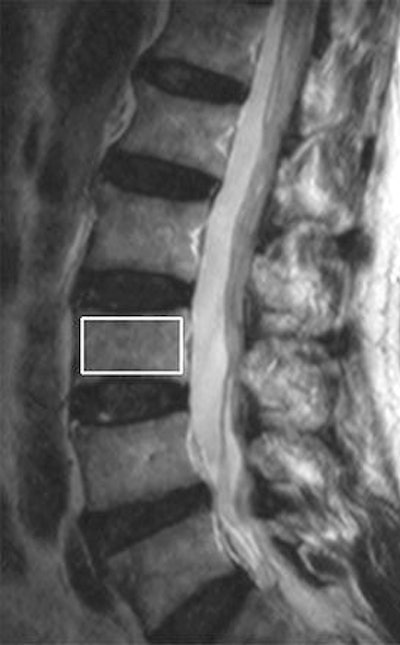

![]() |

| Results of 1H MR spectroscopy of L3 vertebral body in 74-year-old man with osteoporosis (T-score, -3.5). Above, sagittal T2-weighted MR image (3500/120) of lumbar spine shows positioning of the volume of interest for spectroscopy (white box) within the L3 marrow cavity. |